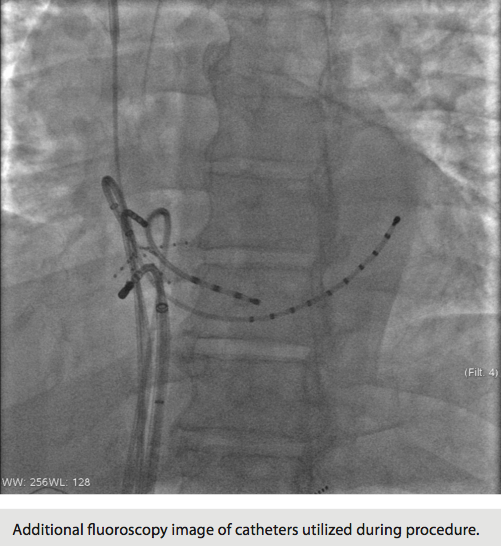

On the day of the procedure, both Dr. Kaufman and Dr. Dixon were in attendance. Monitored anesthesia care was provided to the patient as per department protocol. Three 7 Fr sheaths and an 8 Fr sheath were placed bilaterally in the femoral veins, in addition to a 6 Fr sheath in the right internal jugular and a 5 Fr sheath in the left femoral artery that would be utilized for beat-to-beat blood pressure monitoring. Three 6 Fr quadripolar pacing catheters were advanced to the high right atrium, His bundle, and right ventricular apex. A 5 Fr coronary sinus decapolar catheter was inserted through the right IJ into the coronary sinus for left atrial pacing and recording. After the catheters were placed, the patient developed his index focal atrial tachycardia. The tachycardia cycle length was 440 msec, the R-to-R interval ranged from 440 to 660 msec, the PR interval was demonstrating Wenckebach rhythm, the QRS interval was 80 msec, QT interval 280 msec, the AH interval varied from 180 msec to a Wenckebach cycle length, and the HV interval was 45 msec. Of interest, the earliest atrial depolarization was seen near coronary sinus pole 10-9. However, the His bundle electrogram was also very close to the earliest atrial electrogram. The surface EKG during tachycardia was suggestive of a tricuspid annular tachycardia, so we elected to first perform mapping in the right atrium.

Using the Carto 3 three-dimensional electroanatomical mapping system and the Biosense Webster MEM, we performed fast activation mapping of the entire right atrium. We took approximately 400 points with the PentaRay NAV catheter in less than 10 minutes. Review of these points demonstrated that the earliest atrial electrogram (when compared to CS poles 8-7) was seen at the lateral tricuspid annulus.

Final impressions were focal atrial tachycardias emanating from the lateral tricuspid annulus and the inferolateral tricuspid annulus. A total of 19 applications of radiofrequency energy were delivered, all guided by three-dimensional electroanatomical mapping. Total fluoroscopy time utilized was 22 minutes and 16 seconds with 280 mGy — far below the reportable 2500 mGy. The reduced fluoroscopy time was attributed to the rapid mapping achieved with the PentaRay NAV catheter. Total procedure time (from stick to stop) was three hours and 38 minutes.